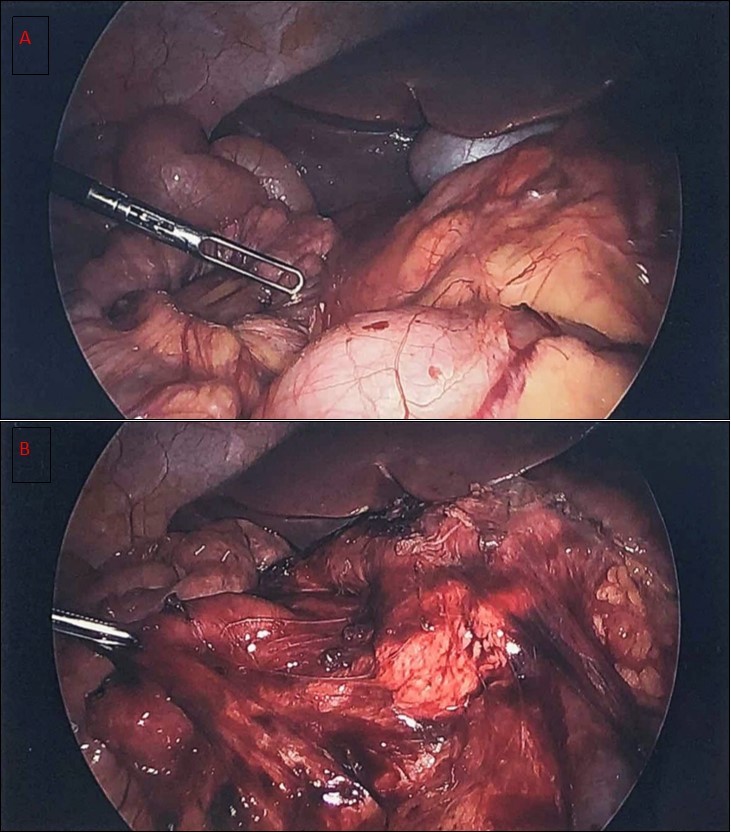

A diagnostic laparoscopy was done showing malrotation with Ladd’s bands constricting the duodenum. Laparoscopic Ladd’s procedure was performed (Figure 3). A three port technique was used. Harmonic scalpel ™ (Ethicon Endosurgery) was used as the energy source to divide the bands. The appendix/cecum that was located in the midline suprapubic area was mobilized by continuing to divide abnormal mesenteric attachments and appendectomy was performed. At completion, small bowel was positioned to the right and large bowel positioned to the left. The duration of surgery was around 100 minutes. Patient had uneventful postoperative course and was discharged on postoperative day 2

Figure 3.a) diagnostic laparoscopy showing Ladd’s bands b) liberation of the duodenum after the Ladd’s procedure with the small bowel to the right of the abdomen